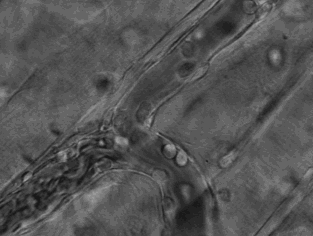

4.这是中性粒细胞追击金黄色葡萄球菌的一个过程。免疫细胞捕捉细菌时超萌!